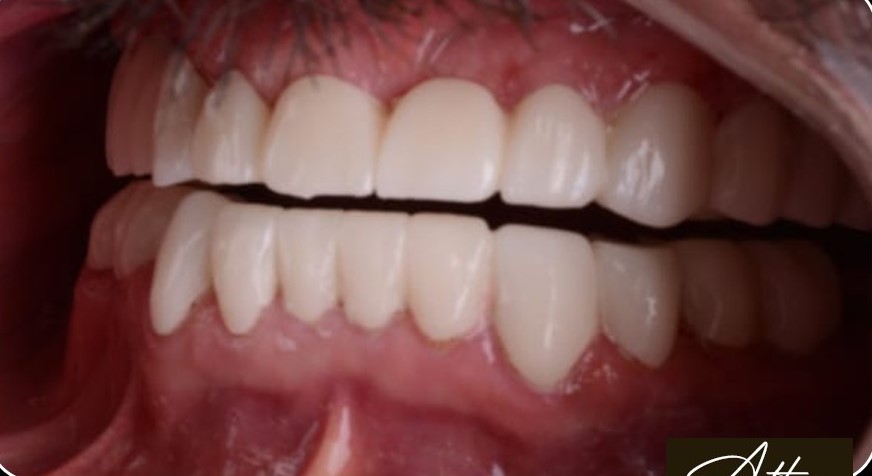

د. حنان ابو الحسن ، مؤسسة Lavender Aesthetic Clinics، هي طبيبة أسنان متخصصة في تركيبات الاسنان ,زراعة الاسنان , حشو عصب ,حشو تجميلي

تميزت برؤيتها اللي بتركز على الجمع بين العلاج الدقيق واللمسة التجميلية، عشان تقدم للمرضى تجربة علاجية مختلفة تجمع بين الصحة، الراحة، والجمال.